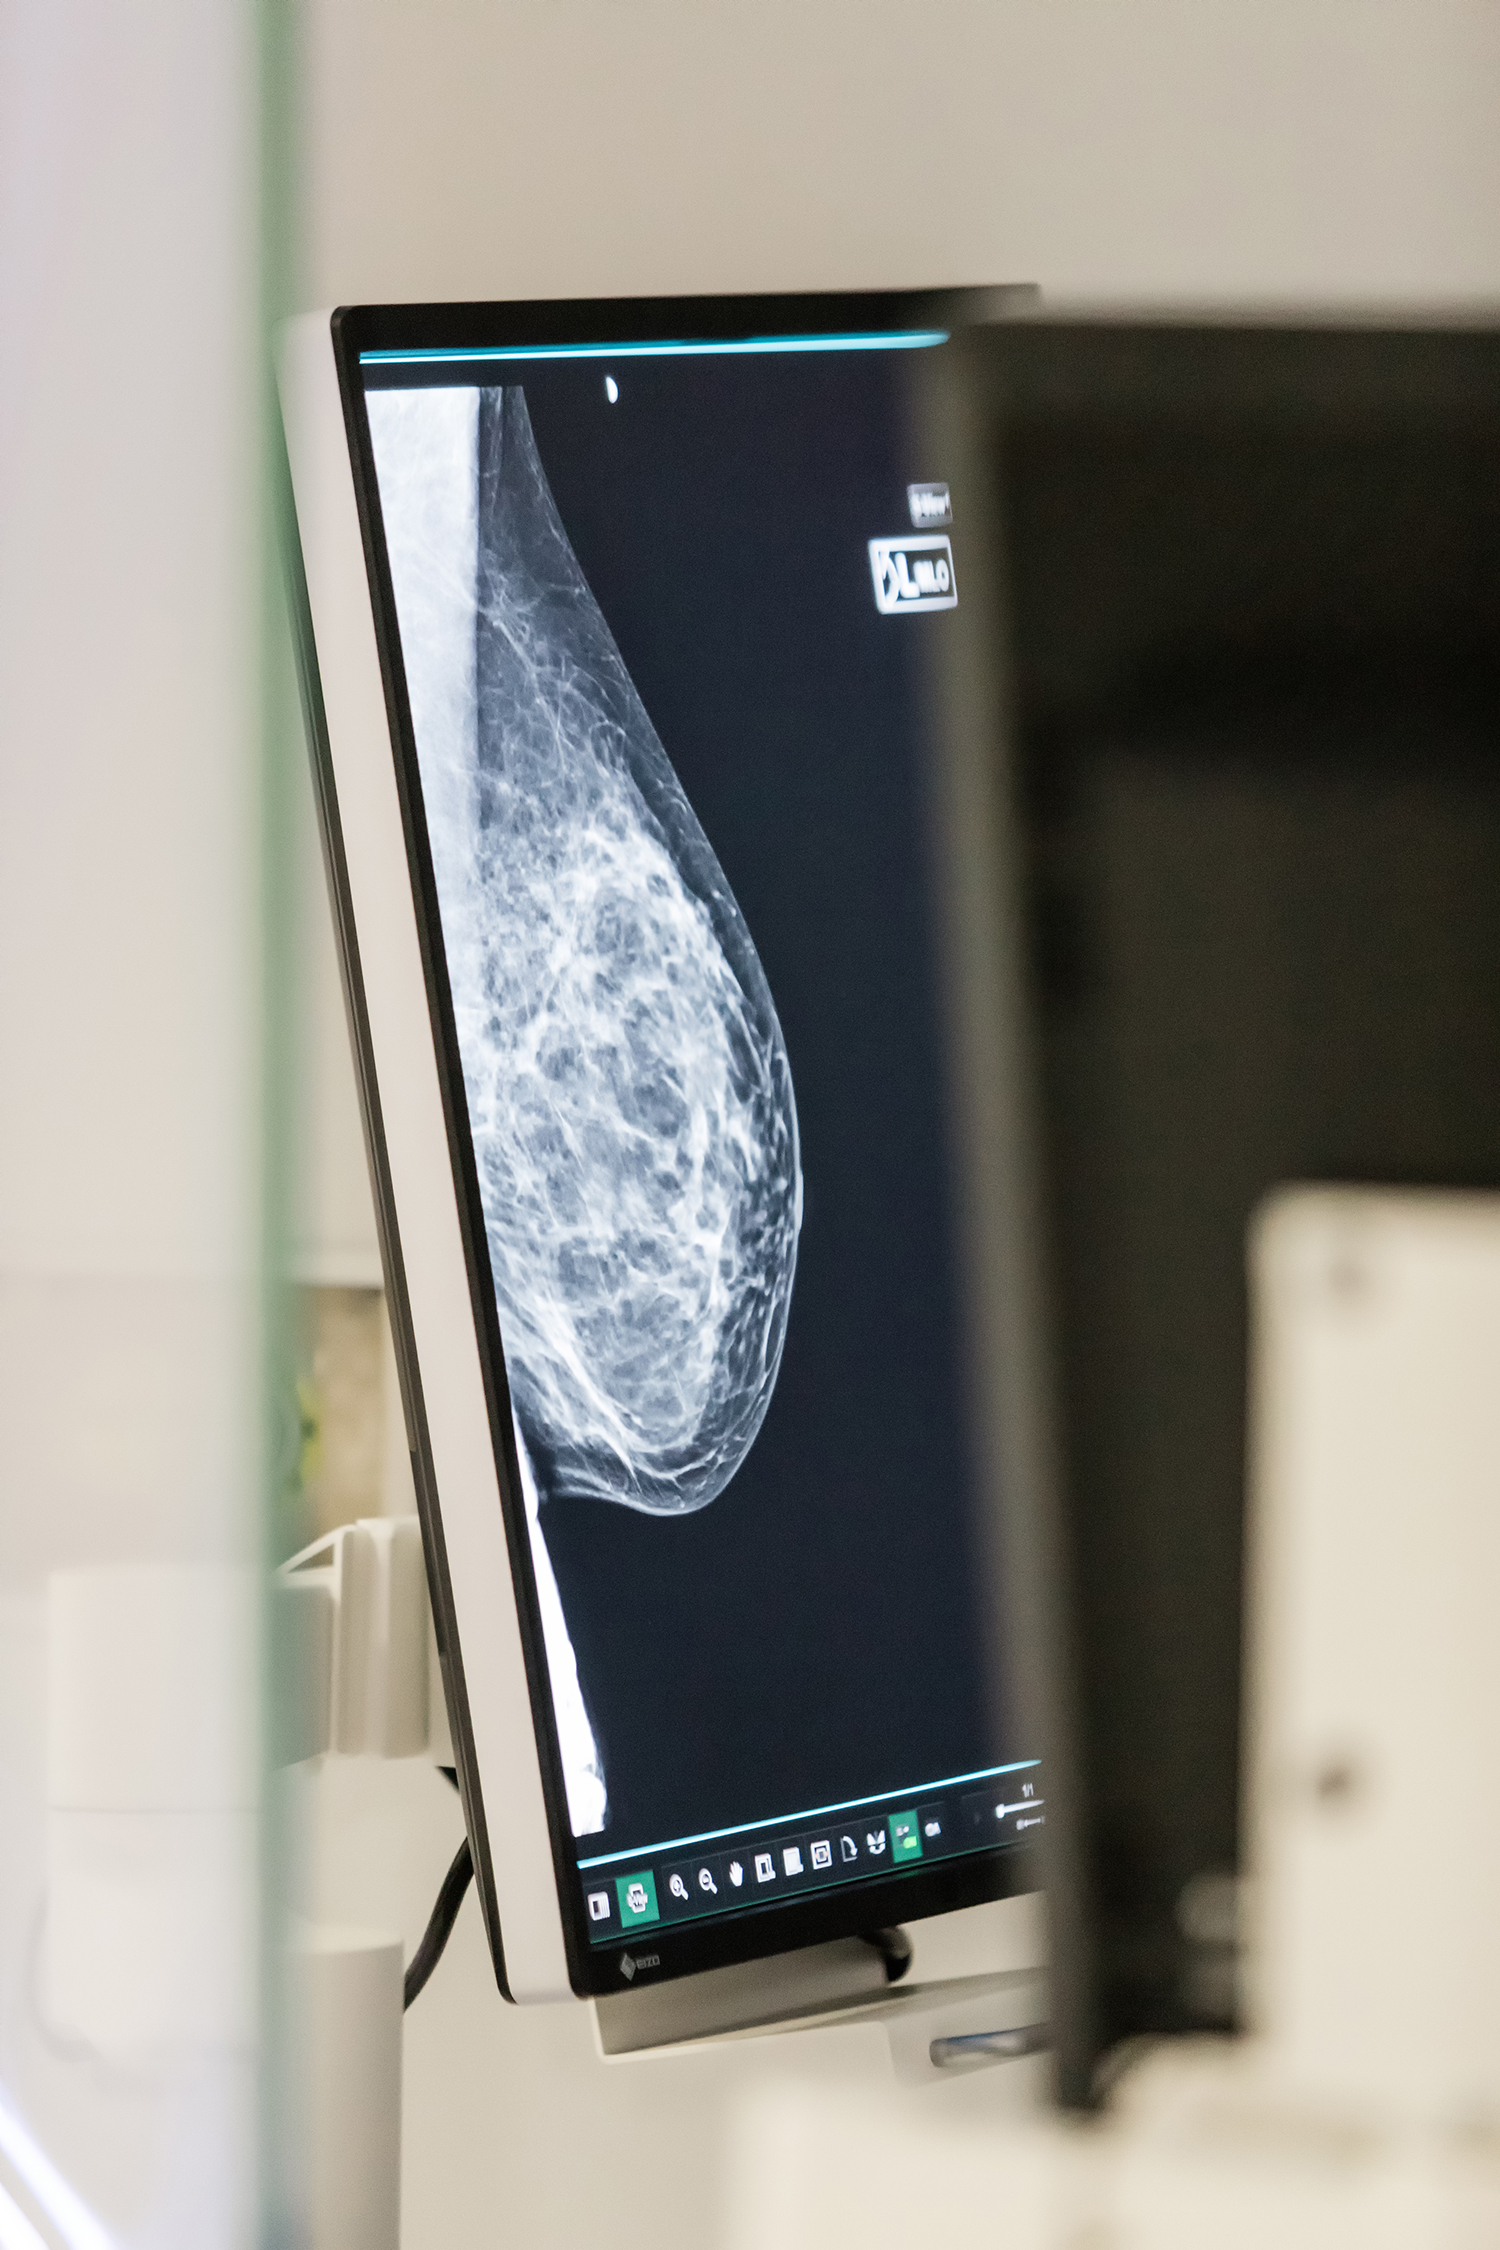

Τεχνολογικά, το νέο Κέντρο Μαστού του ΙΑΣΩ Θεσσαλίας υπερέχει με διαφορά, καθώς διαθέτει τον πρώτο εξειδικευμένο Υπερηχοτομογράφο μαστού LogiqP10, με σημαντικά υψηλότερη ευκρίνεια, με δυνατότητα ελαστογραφίας ShearWave, καθώς και τον υπερσύγχρονο Ψηφιακό Μαστογράφο με δυνατότητα τομοσύνθεσης σε πυκνούς μαστούς, με ελάχιστη ακτινοβολία, ο οποίος υποστηρίζει και στερεοτακτική βιοψία και τοποθέτηση σύρματος hook, με ακρίβεια χιλιοστού για τη σήμανση της πιθανής βλάβης.